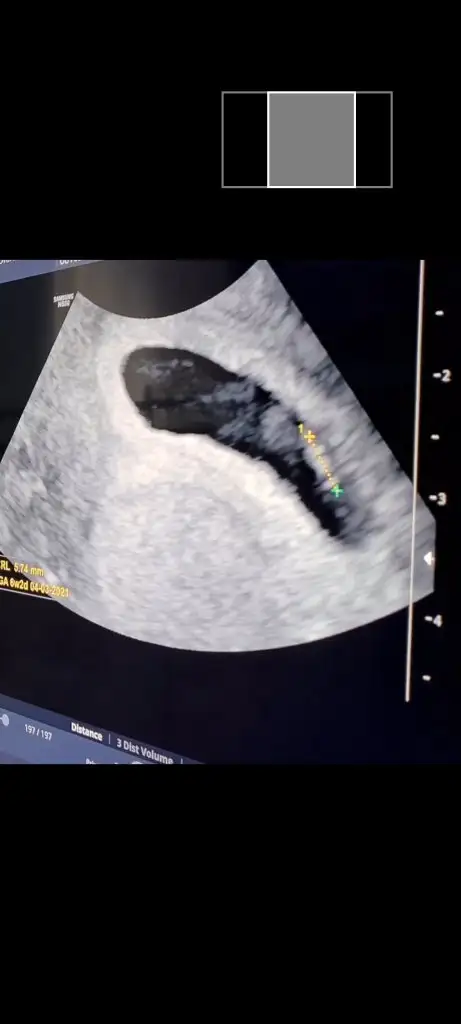

Darısı başınıza insallah sizde görün tez zamanda 6+5 bugunYaa kaç haftalıkmış ne güzel görmüşsünüz keşke bende görsem

Merhaba kızlar simdi doktordan geliyoruz özelde yeni bir doktora basladık ilk randevuydu kalp atışını göremeyiz muhtemelen demisti basta doktor ama gördük cok şükür insallah bundan sonrasıda sağlıkla ilerlerDarısı tüm bekleyen annelerin başına insallah❣

Canım foto varmı bebeğin benim dikkatimi bişey cekti kese içinde bişey var inşallah bebektir üstte çizgi gibiDarısı başınıza insallah sizde görün tez zamanda 6+5 bugun

Garanti olsun diye demek ki, bizim minikte dlktoru baya ugrastrdı atımı yakalayana kadarbenim de randevum yarındı, 6+3te, kalp atisi duyulmayabilir diye onumuzdeki haftaya aldılar.

seninki baya büyük benim üstte çizgi gibi bişey var şimdi dikkatimi cekti sizde gördünüzmü benim keseyivar canım bu hizalı olan bebek yanındaki yuvarlak görünümde yolk kesesi. Benimkinde de bebek düz gözüküyor.